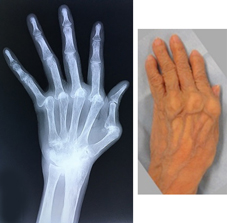

関節リウマチ

リウマチによる手・肘の変形に対する治療は一般的に難易度が高く、また習熟している施設は限られています。当院ではリウマチ手指や肘に対する人工関節手術を積極的に行い、良好な治療成績を得ています。また比較的若年の方で関節面が保たれている場合は可能な限り関節温存手術を行います。当院の担当医はリウマチ指の人工関節手術、人工肘関節手術、人工関節を用いない手指軟部組織形成術や肘関節形成術の経験も豊富です。